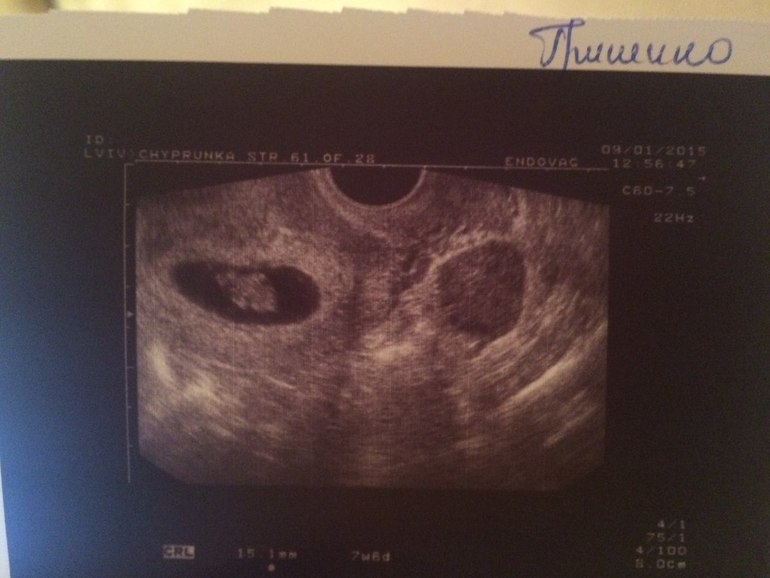

Привет, я к Вам!Всем привет))Решила перебираться уже к вам из зачатия!) Меня зовут Оля, 23 года, буду очень рада общению!))Нам 8 неделек по узд) Сегодня немного испугалась из-за кровянистых выделений, но узи успокоило,отслойки нет,сердечко бьется, мы растем))

А вот и наше фото))